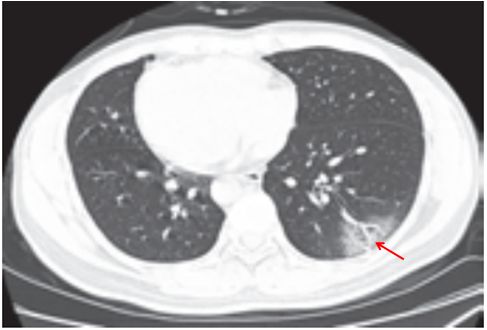

(四)间质性肺炎

肺间质纤维化性疾病包括一系列导致肺间质进行性纤维化的原发性或继发性结缔组织疾病,原发性主要为特发性肺间质纤维化,继发性主要包括系统性红斑狼疮、干燥综合征、类风湿关节炎等。特发性肺间质纤维化、系统性红斑狼疮、干燥综合征三种病变在影像学上表现相似,属于典型的“同影异病”,均表现为肺间质纤维化改变。细菌和病毒均可以引起间质性肺炎。

影像学表现:两肺支气管血管束增多,网格状及小点状影,周围夹杂多发蜂窝状囊状影、肺气肿及牵拉性支气管扩张,相应胸膜下小叶间隔增厚(图 3-18)。

图片